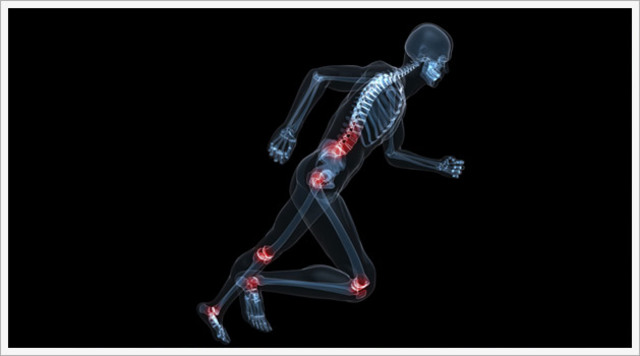

The bone and marrow that make up the fetus's skeletal system are continuing to develop in this week. The bones and muscles are continuing to grow too.

The fetus has learned to breathe. It starts to inhale and exhale small amounts of amniotic fluid which helps the lungs to develop and grow. It also has more developed facial muscles.